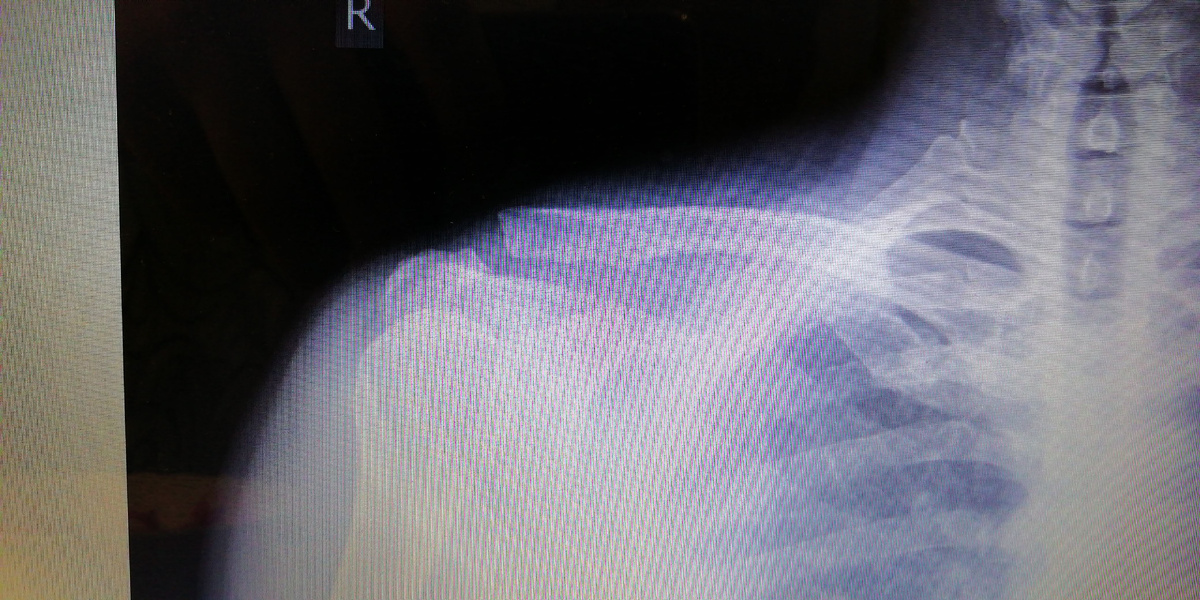

Самостоятельно доехал до травмпункта. Врач при пульпации и по снимку ренгена поставил диагноз: перелом большого бугорка плечевой кости и напряжение связок ключицы. Операция не требовалась. Только длительное восстановление в повязке (около 2 месяцев), далее реабилитация.

Травма правой ключицы (снимок левой ключицы не удолось взять)